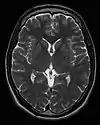

Neuroimaging

MRI is the investigative tool of choice for neurological cancers over CT, as it offers better visualization of the posterior cranial fossa, containing the brainstem and the cerebellum. The contrast provided between grey and white matter makes MRI the best choice for many conditions of the central nervous system, including demyelinating diseases, dementia, cerebrovascular disease, infectious diseases, Alzheimer's disease and epilepsy.[26][27][28] Since many images are taken milliseconds apart, it shows how the brain responds to different stimuli, enabling researchers to study both the functional and structural brain abnormalities in psychological disorders.[29] MRI also is used in guided stereotactic surgery and radiosurgery for treatment of intracranial tumors, arteriovenous malformations, and other surgically treatable conditions using a device known as the N-localizer.[30][31][32] New tools that implement artificial intelligence in healthcare have demonstrated higher image quality and morphometric analysis in neuroimaging with the application of a denoising system.[33]